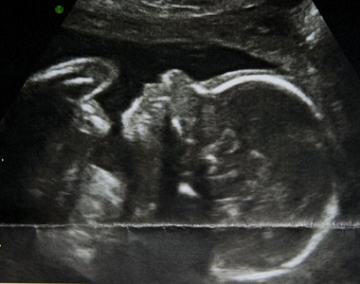

Eva (28 let, 39. týden těhotenství, druhorodička, termín porodu březen 2015)

Miminko má mít nyní obvod hlavičky asi 31cm. Minule jsem řešila všechno možné, jen ne svou přípravu. Teď se snažím opravdu připravit, takže jsem vážně, vážně zvědavá, zda pocítím nějaký nezanedbatelný rozdíl. Jistě, rozdíl by měl být už jenom v tom, že jsem druhorodička. I to bude mít vliv, ale věřím, že čajíčky, masáže, Aniball atd. jsou dobré věci a z nějakého důvodu jsou na jejich používání dobré ohlasy. Necháme se překvapit.

Jinak, váhový deficit miminka se opět trochu zlepšil a zas jsme se přiblížili normě, takže by mělo být vše v pořádku.